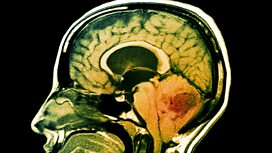

Brain Tumours

In today's medical, we look at brain tumours.